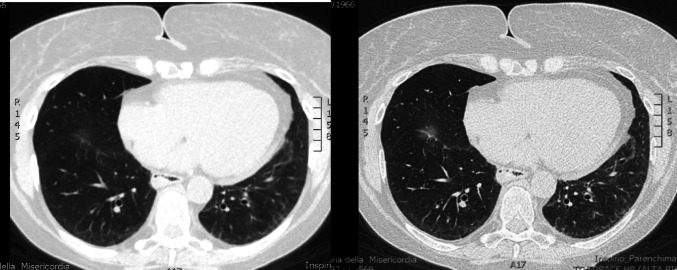

系统性硬化症(SSc)和淀粉样变是罕见的复杂疾病,损害多个器官的功能,每种疾病都有不同的致病机制:SSc的自身免疫和淀粉样变的错误折叠蛋白沉积。我们报告了第一例57岁女性并发SSc和系统性AL淀粉样变并多器官受累的病例,其中淀粉样变治疗导致SSc症状显著改善。患者于2023年夏季出现疲劳、用力性呼吸困难、上腹部疼痛和晕厥发作。调查显示左心室厚度轻度增加,NT-proBNP和肌钙蛋白升高,冠状动脉造影阴性。随后,她被诊断为SSc,多器官受累,活检证实为系统性AL淀粉样变。采用改良的Dara-CyBorD方案治疗可改善SSc症状,特别是在呼吸困难和皮肤受累方面。这是首次报道的SSc与系统性AL淀粉样变并存的病例。该患者对淀粉样变治疗反应良好,提示潜在的重叠治疗益处。多学科的方法是必不可少的,需要进一步的研究来探索这两种罕见疾病之间的治疗相互作用。

Systemic sclerosis (SSc) and amyloidosis are rare, complex conditions that impair the function of multiple organs, each with distinct pathogenic mechanisms: autoimmunity for SSc and misfolded protein deposition for amyloidosis. We present the first documented case of a 57-year-old woman with coexisting SSc and systemic AL amyloidosis with multi-organ involvement, in which treatment for amyloidosis led to a notable improvement in SSc symptoms. The patient presented experiencing fatigue, exertional dyspnea, epigastric pain and syncopal episodes in the summer of 2023. Investigations revealed mild increase in left ventricle thickness, elevated NT-proBNP and troponin with negative coronary angiography. She was subsequently diagnosed with SSc with multi-organ involvement and systemic AL amyloidosis confirmed by biopsy. Treatment with a modified Dara-CyBorD protocol led to improvement in SSc symptoms, especially in terms of dyspnea and skin involvement. This is the first reported case of SSc coexisting with systemic AL amyloidosis. The patient responded well to therapy for amyloidosis, suggesting potential overlapping treatment benefits. A multidisciplinary approach was essential, and further studies are needed to explore therapeutic interactions between these two rare diseases.